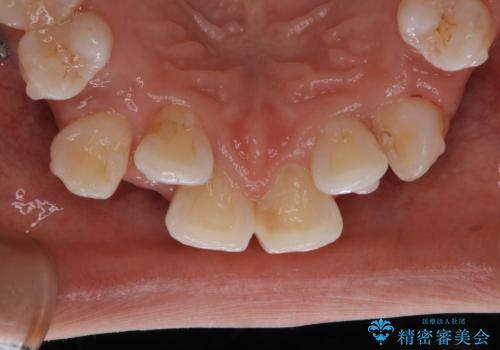

インビザラインで矯正中のコーヒーによる着色をきれいに除去

- インビザライン中に、コーヒーによる着色が気になるとのことでした。PMTC60分コースを行いました。

PMTC(保険外治療)は、毎日の歯磨きで落としきれない汚れや、コーヒ、紅茶・タバコのヤニなどの着色も除去します。目には見えない歯と歯の間・歯肉の境目・インビザライン中はアタッチメント周囲などに残っているプラーク(歯垢)もしっかり取り除きます。PMTCでは専門的な機械や材料を使用して、徹底的に汚れを除去するため、虫歯・歯周病・口臭予防などにつながります。